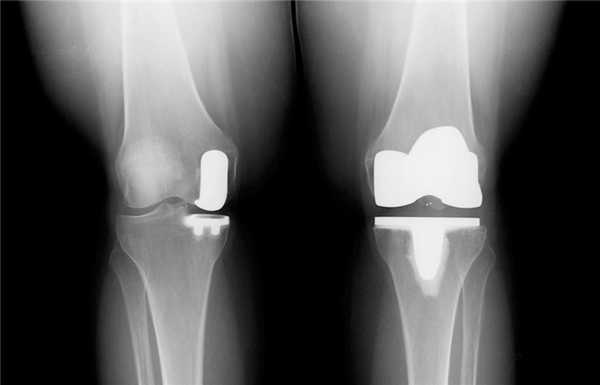

Имплант на рентгене.

Как это выглядит после операции.

Две техники операции у одного пациента.

Одномыщелковая замена сустава на рентгене.